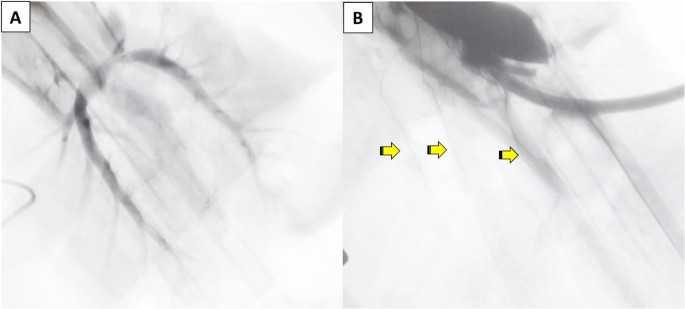

Our modified EVLP platform successfully directed perfusion into two separate outflow tracts with differential flow rates (Fig. 2A). Six swine lungs were procured with the bronchial arteries intact and mounted onto our modified EVLP platform (Fig. 2B-C). Average cold ischemia time was 30.5 ± 7.2 min from cold flush to warm reperfusion. Cold ischemic times ranged from 21 to 41 min. After flushing, and warming, PA-only circulation was commenced. First, angiography was performed to confirm successful procurement of the bronchial arteries, which were intact in all 6 lungs (Fig. 3; Supplementary Video 1).

Angiographic assessment of pulmonary and bronchial circulation was performed with a mobile fluoroscopic C-arm (Phillips, Amsterdam, Netherlands) via cine capture during hand injection of 50 cc of a 50/50 mixture of normal saline and iodinated contrast. The pulmonary artery circulation was imaged first, then the bronchial circulation in isolation with the EVLP circuit paused.

Fluoroscopic angiography performed while on EVLP using iodinated contrast perfused into the (A) PA only, and (B) into the aortic cannula directed towards the bronchial arteries (highlighted with yellow arrows).